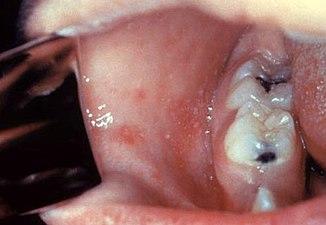

Koplik's spots seen inside the mouth are diagnostic for measles, but are temporary and therefore rarely seen.[26] Koplik spots are small white spots that are commonly seen on the inside of the cheeks opposite the molars.[25] They appear as "grains of salt on a reddish background."[28] Recognizing these spots before a person reaches their maximum infectiousness can help reduce the spread of the disease.[29]